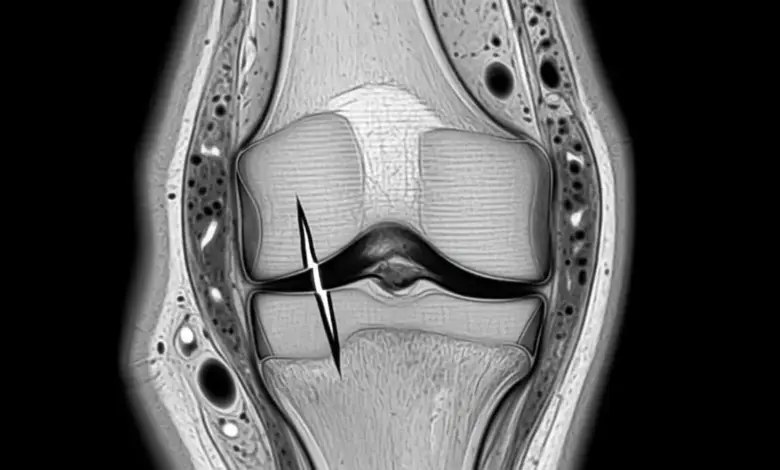

Ao analisar exames de ressonância e correlacionar com os sintomas dos pacientes, a lesão radial se destaca como a mais agressiva para a função do menisco.

Nesse tipo de ruptura, o corte é feito no sentido transversal, como se alguém abrisse o menisco “de dentro para fora”, dividindo a estrutura.

Na prática do dia a dia, costumo explicar ao paciente que a lesão radial, principalmente quando acomete a região mais central do menisco, se comporta quase como se uma parte inteira tivesse sido retirada.

A peça deixa de trabalhar como anel de distribuição de carga e a cartilagem passa a receber impacto concentrado em áreas menores.

Mas para definir qual pior tipo de lesão de menisco naquele caso específico, a ressonância magnética costuma ser o exame mais útil, pois mostra o desenho da ruptura, se ela é radial, horizontal, vertical, complexa e se há outras estruturas comprometidas, como ligamentos e cartilagem.